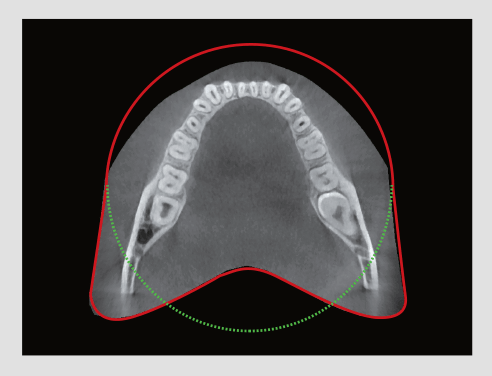

El innovador FOV proporciona un volumen en forma de arco que muestra una vista más amplia de la dentición en comparación con otros dispositivos del mismo FOV.

Normalmente, una imagen de 10x8.5 muestra el diente No.8. Sin embargo, cuando los terceros molares están tumbados sobre su lado hay una gran posibilidad de que el diente se corte de la imagen.

El “volumen en forma de arco” elimina esta posibilidad y muestra el área de dentición oculto.